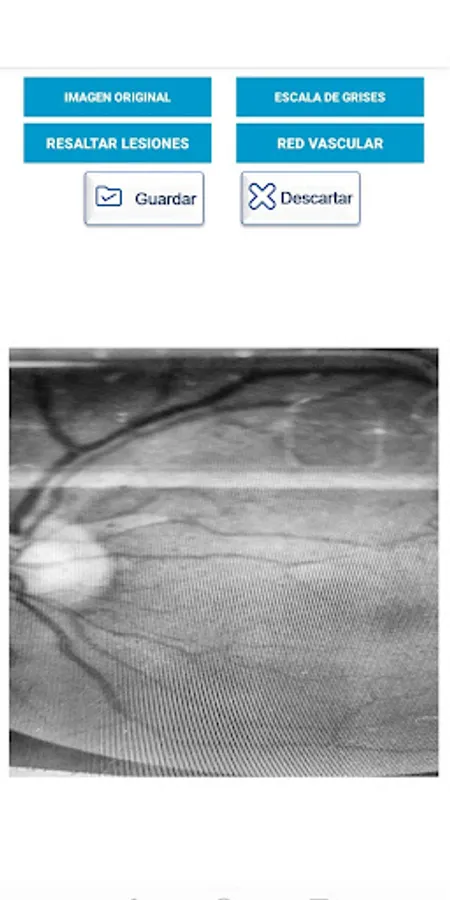

Capture and process fundus images with a mobile device using artificial vision techniques, in order to improve these images and thereby support physicians in the diagnosis of diabetic retinopathy. To use this application it is necessary to have a PanRetinal 2.2 lens and, preferably, a coupling device between the lens and your Smartphone

Exploracion Screenshots